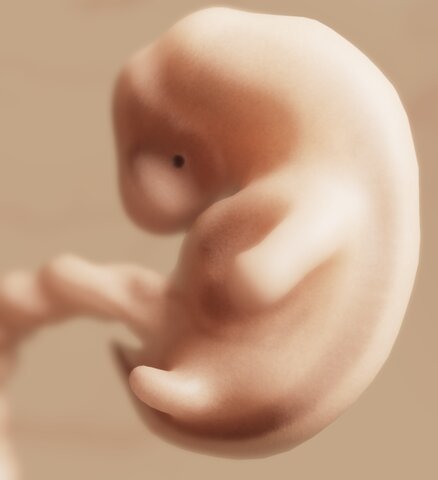

La mayoría de los órganos comienzan a formarse, poco después empieza a desarrollarse la zona que será el cerebro y la médula espinal

• Semana 6

Semana 6

Allanamiento terminal de las yemas para formar placas de manos y pies

Se forma un pequeño corazón de dos cámaras que parece un pequeño tubo retorcido

El embrión flota en un fluido (líquido amniótico) que se almacena en una bolsa (saco amniótico) que ofrece un espacio para que el embrión puedo crecer libremente y contribuye a proteger al feto de lesiones

La placenta forma diminutas proyecciones pilosas(vellosidades) que se extienden hacia el interior de la pared uterina